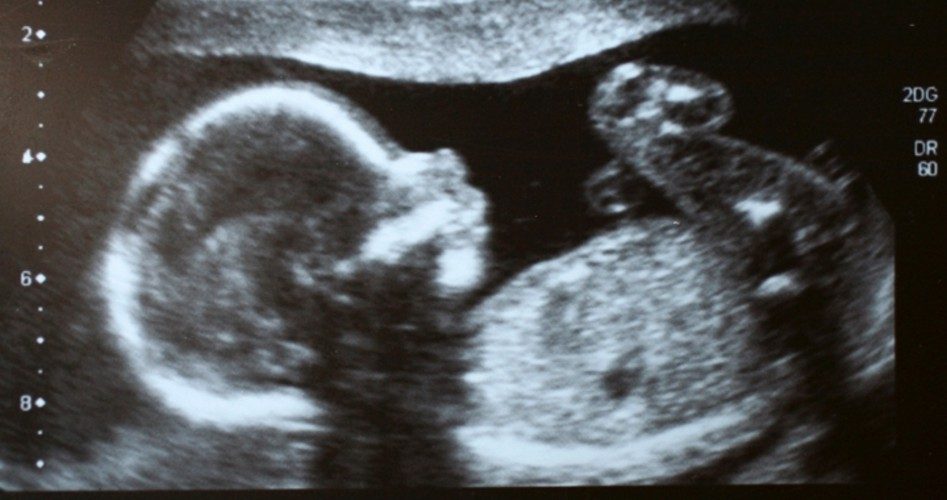

The Oklahoma Senate passed a pro-life bill that would ban abortions once a fetal heartbeat or fetal brainwaves are detected. The bill is likely to pass the Republican-controlled Oklahoma House and be signed into law by pro-life Governor Kevin Stitt, a Republican.

“This is a commonsense measure that directs doctors to recognize life just as they do death with the presence or lack of a heartbeat or brainwaves,” said State Senator Paul Scott, R-Duncan, who authored the legislation, the Purcell Register reports.

SB 1859 virtually prohibits all abortions after six weeks, without exception for rape, incest, or risk to mother’s health — though more than 30,000 doctors declared in a letter published at The Public Discourse that abortions are rarely ever medically necessary to save a mother’s life, particularly once the pregnancy has progressed to the third trimester: